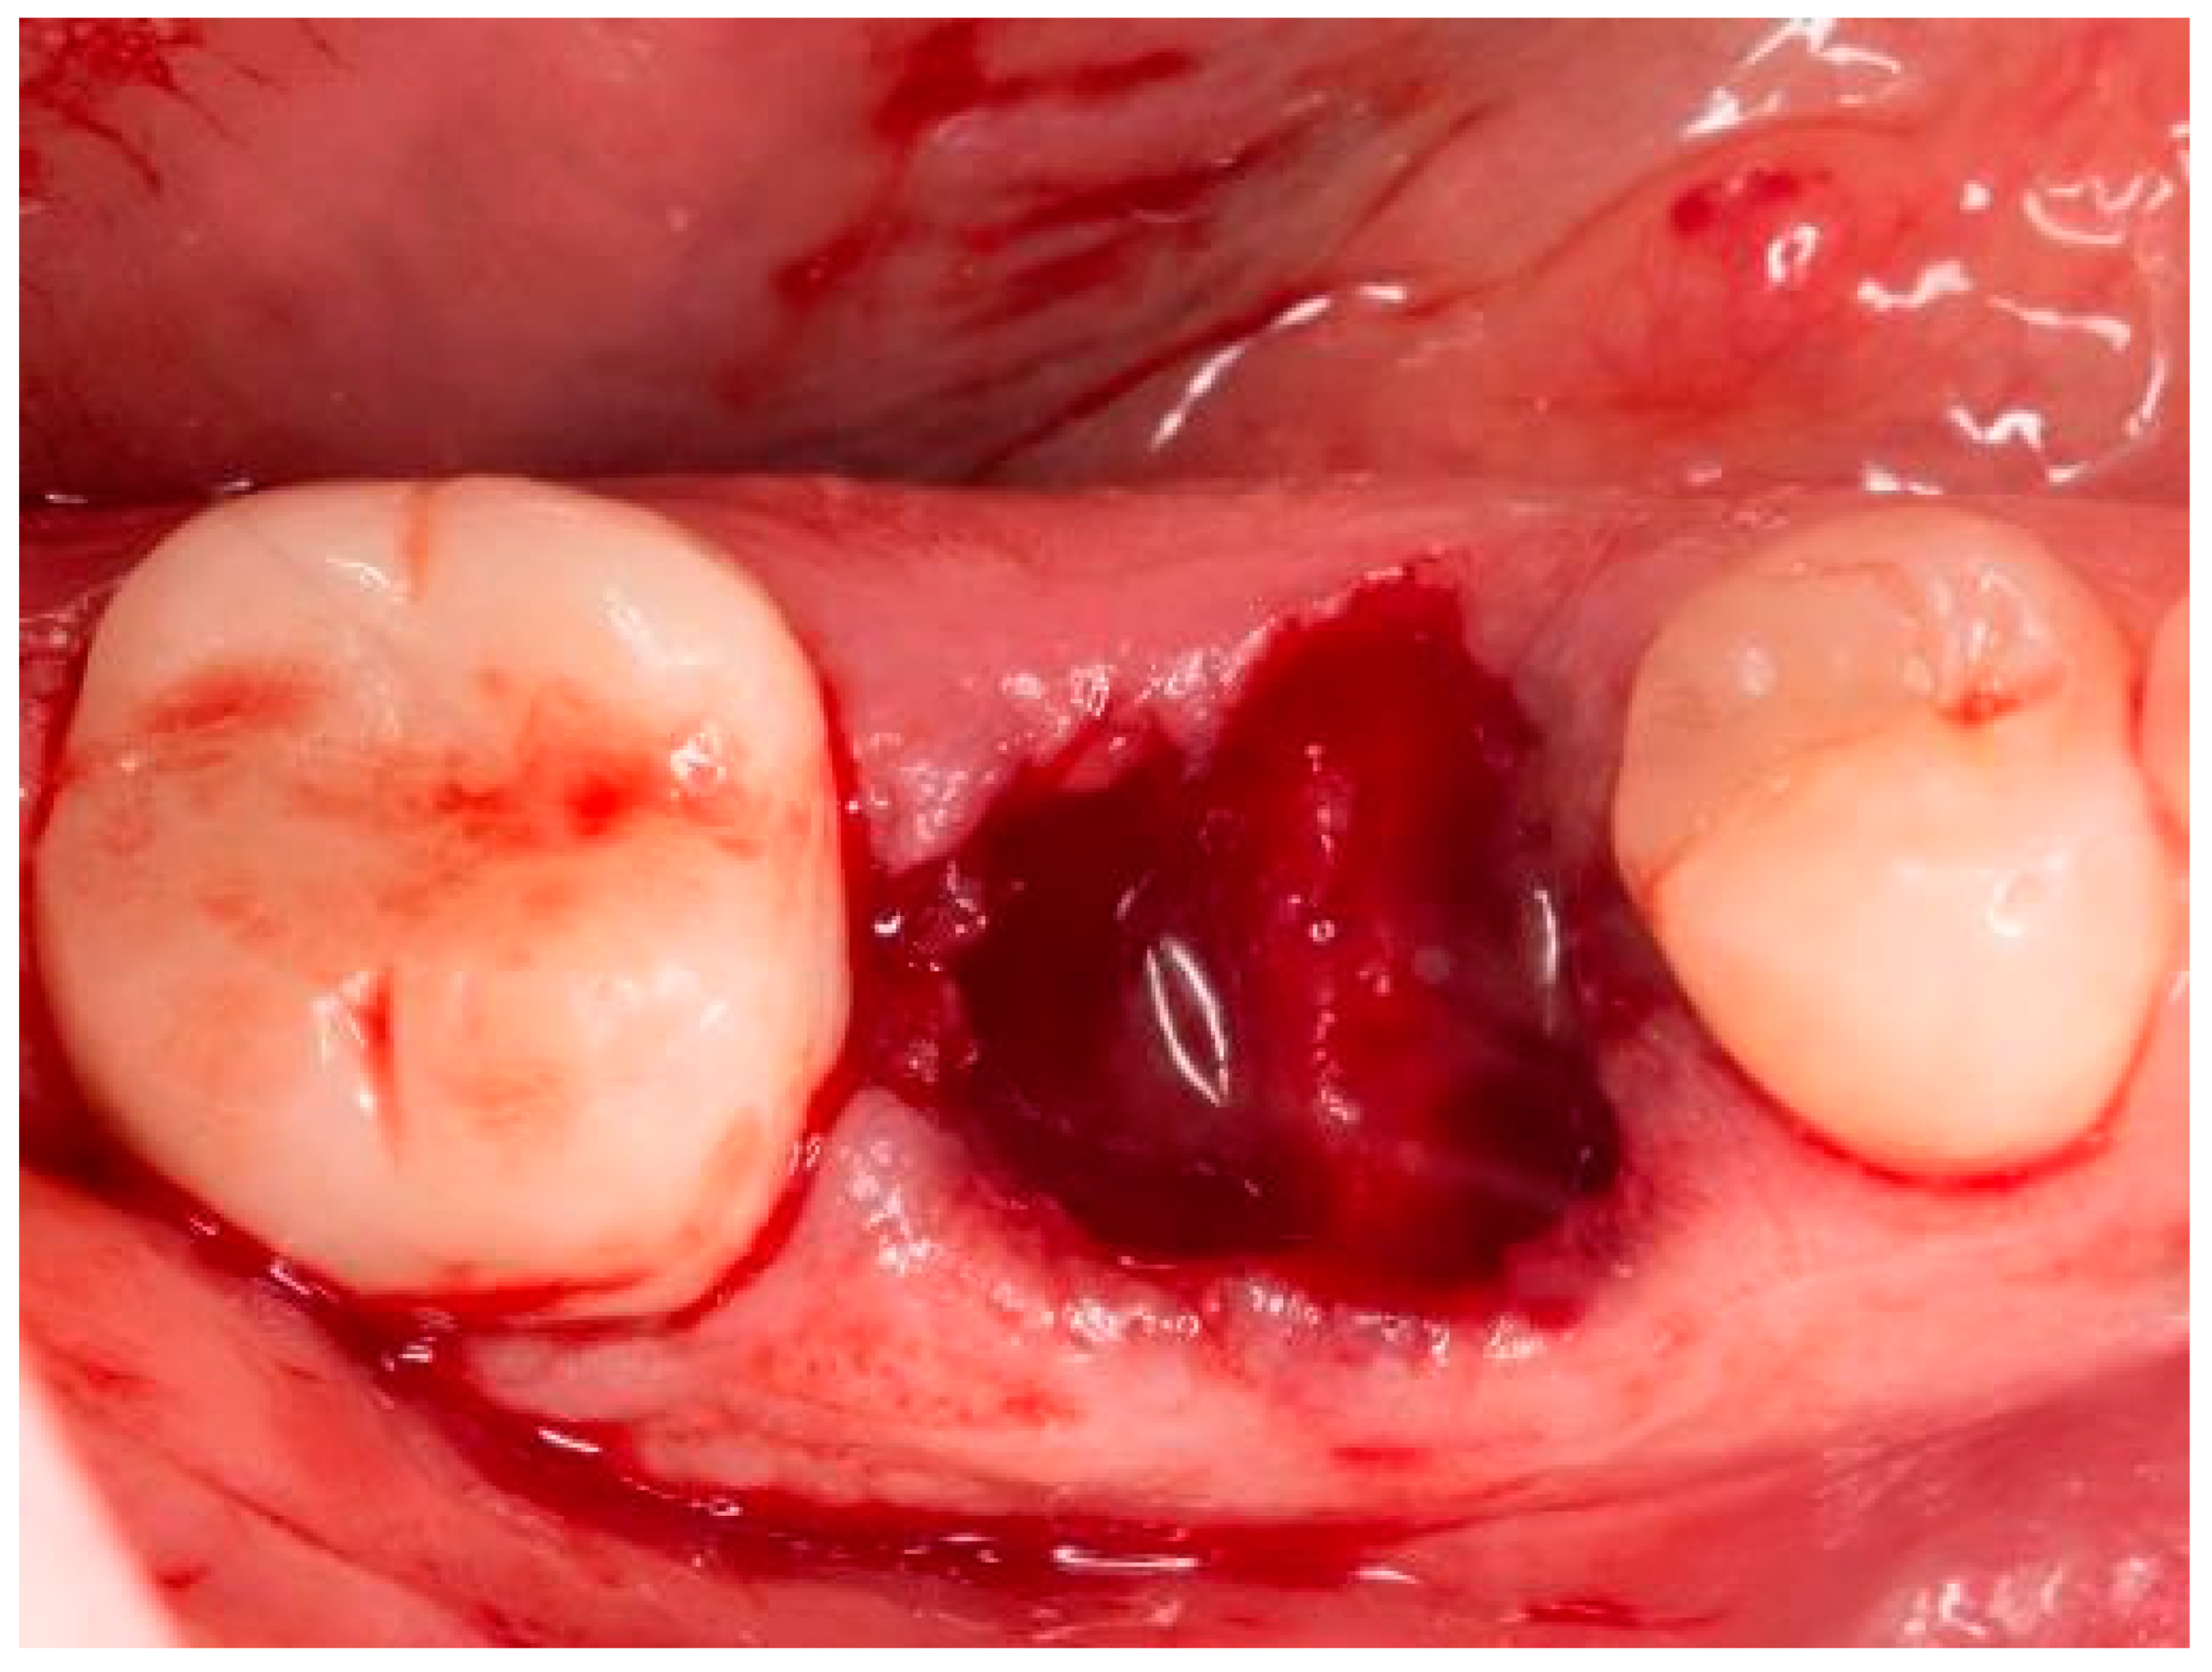

Figure 1.

Socket of tooth 46 after tooth extraction.